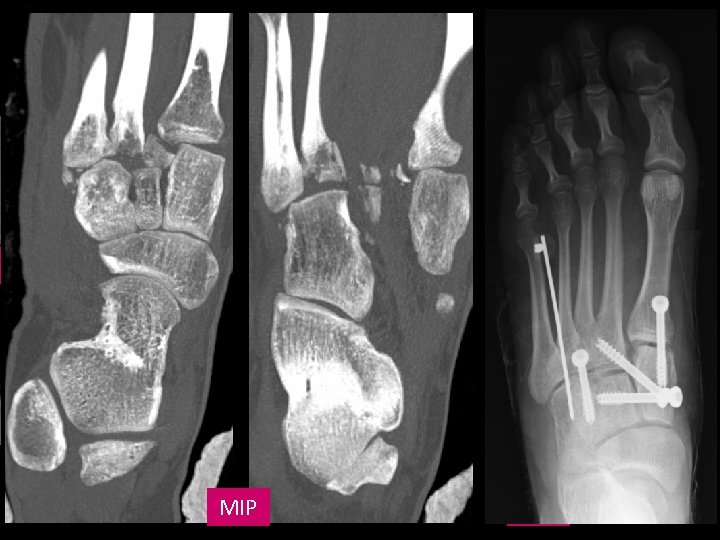

CORONAL MIP CORONAL A LA ART. CUNEOMETATARSIAN VR A

CONCLUSIONES õ õ õ õ Ligamento de Lisfranc (C 1 -M 2): soporte más potente. Incidencia: 1/55. 000 personas (<1% de todas las fx). Varones (2: 1). Clasificación: Myerson et al. Hasta 20% pasan desapercibidas. Rx: AP, lateral y oblicua 30º. Carga. TC: coronal a la art. cuneometatarsiana õ detección lesiones sutiles o desapercibidas en Rx. õ valoración de fragmentos y su desplazamiento. õ Tto: õ Conservador: no fracturas, no desplazamiento. õ Qx: reducción y fijación con agujas. BIBLIOGRAFÍA 1. Siddiqui NA, Galizia MS, Almusa E, Omar IM. Evaluation of the Tarsometatarsal Joint Using Conventional Radiography, CT, and MR Imaging. Radio. Graphics 2014; 34: 514– 531. 2. Watson TS, Shurnas PS, Denker J. Treatment of Lisfranc Joint Injury: Current Concepts. Journal of the American Academy of Orthopaedic Surgeons, December 2010; Vol 18, No 12. 3. Montejo Rodrigo E, Pastor Ausin E, Ereño Ealo MJ, Sancho Garaizábal B, Carrascoso J, Armendariz Tellitu K. Fracturaluxación de Lisfranc. Aportación del TCMD. Presentación electrónica educativa, Seram 2012.